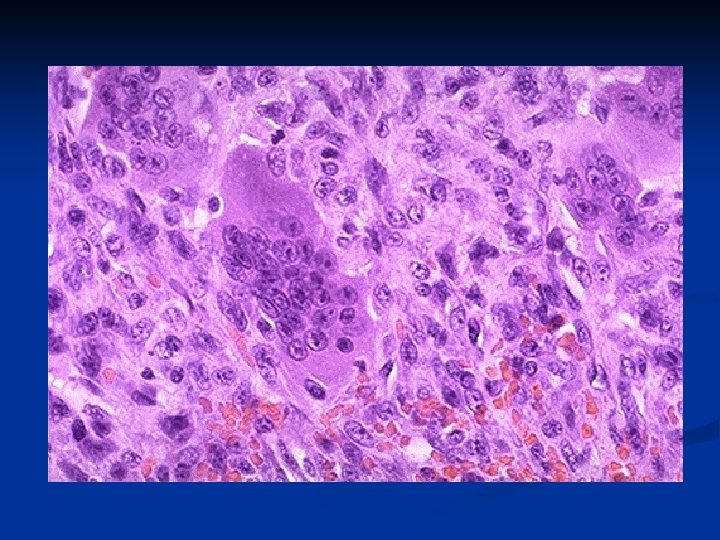

Microscopy: 1. plump, spindly, and oval stromal cells 2. multinucleated tumor giant cells which are formed by fusion of the stromal cells n Differential diagnosis: n reparative granulomas n brown tumors of hyperparathyroidism n the lytic phase of Paget's disease n aneurysmal bone cyst n